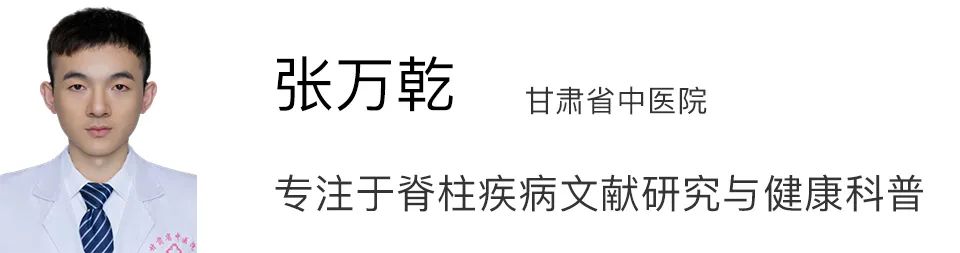

图一:LDH 患者 L4/5 在出现症状 5 个月后发生自发性消退

患者女,29 岁,因「右小腿疼痛并感觉异常」就诊,大小便正常。起始腰椎磁共振提示腰 L4/5 突出并椎管狭窄,神经根压迫严重(左图)。患者选择保守治疗,5 个月后复查 MRI(右图)发现突出的椎间盘自发性吸收了,并且临床症状基本缓解。